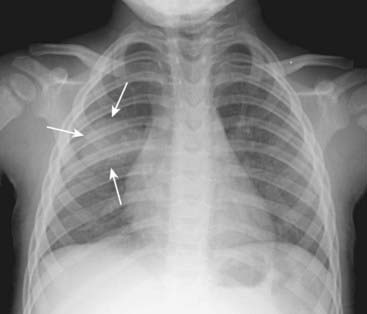

Figure 7-6 Round pneumonia.

A soft tissue density that has a rounded appearance (solid white arrows) is seen in the right midlung field. The patient is a 10-month-old baby who had a cough and fever. This is a characteristic appearance of a round pneumonia, most common in children and frequently due to either Haemophilus, streptococcal, or pneumococcal infection.